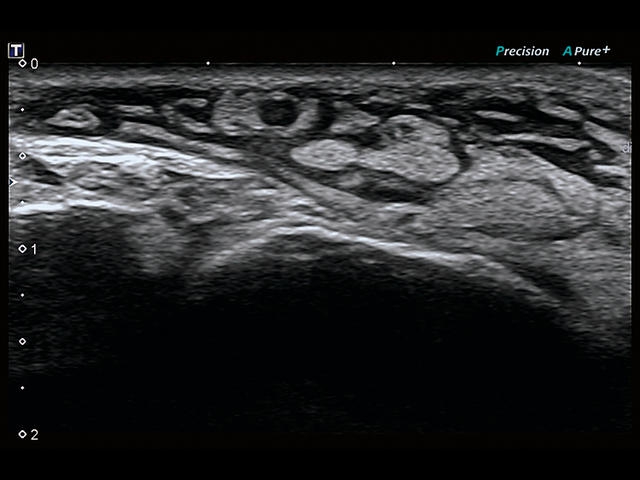

Aplio 500 – ультразвуковой сканер премиум класса, сочетающий в себе быстродействие диагностики и отличное качество визуализации. Более 30 датчиков на выбор, в т.ч. матричные, монокристаллические, 4D, эндоскопические для любых типов исследований. Ультразвуковой сканер позволяет изучать анатомические структуры в высоком разрешении.

Обновленная версия легендарного УЗ-сканера. Стационарный аппарат экспертного класса Aplio 500 Toshiba NEW, визуализирует анатомические структуры в высоком разрешении. Модель позволяет выявить микрокальцификаты, новообразования, нарушения в работе сердца, сосудов и мышц. Присутствует функция виртуальной эндоскопии, 4D-сканирования, эластометрии тканей, УЗИ с контрастированием. За повышение качества изображения отвечают технологии ApliPure и Superb Microvascular Imaging. Первая задействует возможности пространственного и частотного кодирования, формирует цельный визуальный ряд с сохранением клинических маркеров. Вторая улучшает отображение микрососудистого русла, используя доплеровский эффект. Модель оснащена 21-дюймовым монитором, имеет 4 активных порта. Возможно подключение педиатрических, интраоперационных, лапароскопических и чреспищеводных датчиков.

• D-THI.Режим дифференцированной тканевой гармоники, повышающий качество визуализации глубоко расположенных тканей. Получаемое изображение отличается высокой четкостью, не содержит дефектов в виде «заснеженных» и размытых участков.